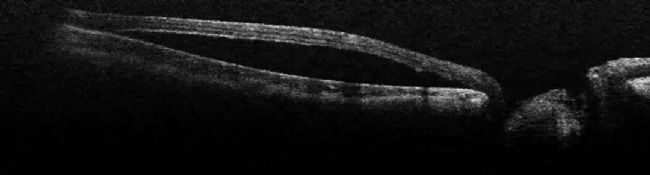

一名年輕女孩出現視盤凹陷。術中 OCT 顯示視盤旁邊的視網膜被擠出,中心凹脫離(圖 13)。為了治療患者,醫生對其進行了玻璃體手術。玻璃體被剝離,視網膜被稍微抬起。術中 OCT 控制了整個操作過程,避免了過大的壓力(圖 14)。

圖 13:術中 OCT 顯示視盤旁邊的視網膜被擠壓,中心凹脫離。圖片由 Nikolaos Bechrakis 教授提供。

圖 14:玻璃體脫離,視網膜被稍微抬起。圖片由 Nikolaos Bechrakis 教授提供。

這次手術的計劃是進行內界膜(ILM)剝離。在注射了內層緣膜染料后,用 25g 儀器剝離了內層緣膜(圖 15)。使用改良的黃斑孔倒置內膜瓣技術后,液體進入視網膜和視網膜下方的區域被密封。術中通過 OCT 確認了 ILM 的適當位置。術后,積液慢慢減少,視力也有所提高。

圖 15:涂抹 ILM 染料后,用 25g 儀器剝離 ILM。圖片由 Nikolaos Bechrakis 教授提供。

圖 16:術中 OCT 使外科醫生能夠確認 ILM 處于適當位置。圖片由 Nikolaos Bechrakis 教授提供。